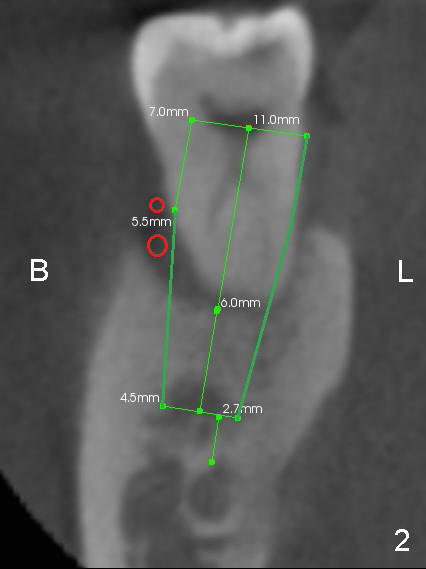

CT coronal sections at the mesial root of #31 show that a 7x17 (Fig.2) or 7x14 mm (Fig.3) implant does not look too large for the alveolar bone buccolingually. The large implant is able to help close the large socket (mesial (Fig.1,4) and buccal (Fig.2,3) aspects), reducing the amount of bone graft (red circles) placed. In contrast, the buccolingual width of #30 is narrower (Fig.9 CT coronal section), allowing a smaller implant (6x17 mm by design (Fig.9), 5x17 mm clinically (Fig.4)).